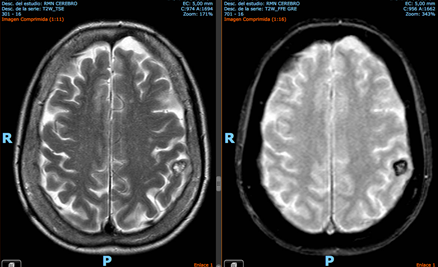

Ej. 2: Paciente de 70 años, antecedente de pérdida de memoria, con IRM con cavernoma incidental poscentral izquierdo. No se indicó tratamiento.